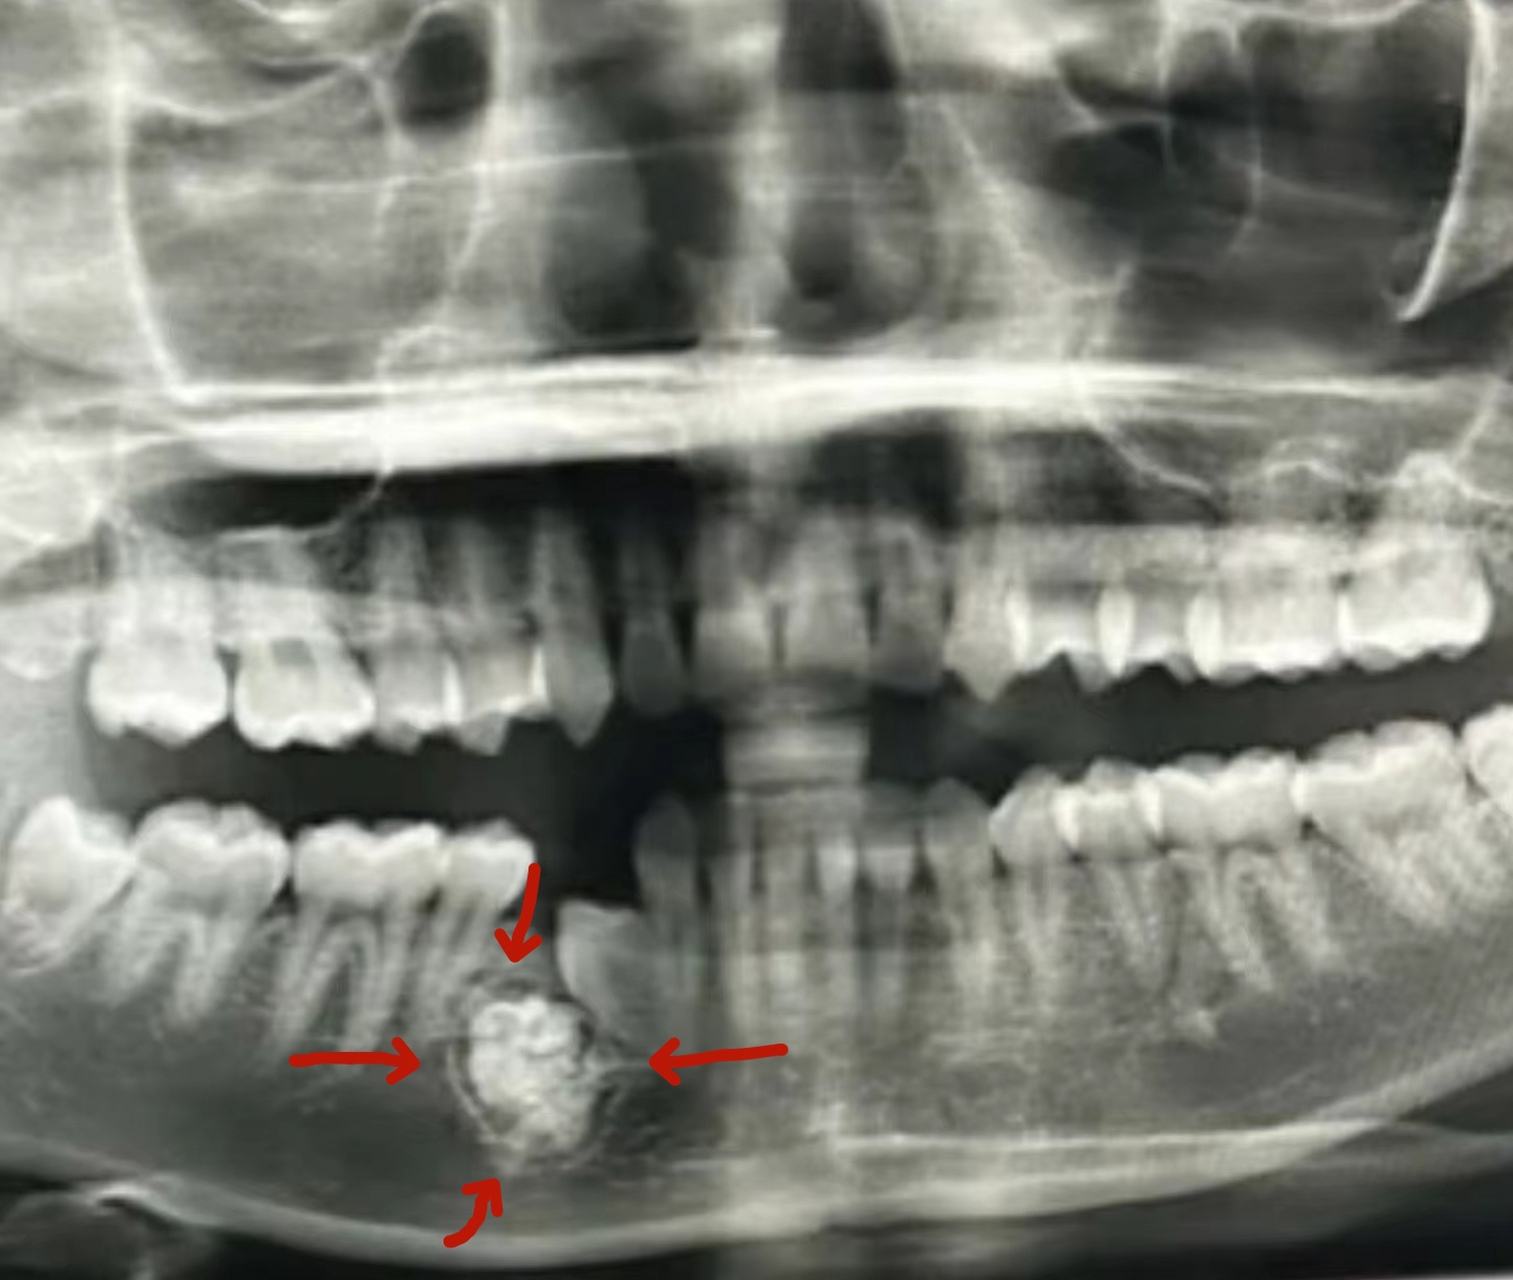

颌骨肿物(牙瘤)

图片尺寸1080x808